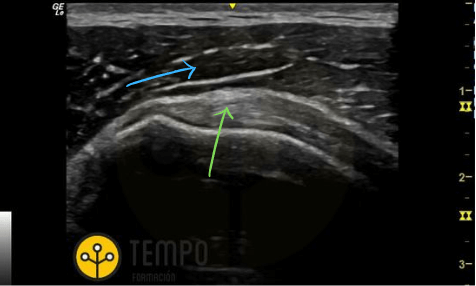

Hipoecoico

"Es una zona o estructura con un bajo nivel de Gris, siendo relativo a lo que se compare."

Es importante dejar claro esta última parte de "siendo relativo a lo que se compare". Por ejemplo, ¿qué flecha correndonde a la estructura más hipoecoica en la siguiente imagen?

Exacto, la flecha verde, porque su nivel de gris es mas bajo (oscuro) que la flecha azul.

Hiperecoico

"Es una estructura con un alto nivel de Gris, representándose con un color blanco, siendo relativo a lo que se compare."

Si en la definición anterior hablábamos de aquello que es más oscuro, en esta ocasión hablamos de qué es más claro/blanco. En ecografía lo más hiperecoico que puedes encontrar es una cortical o tejido conectivo.

Cogemos la misma imagen anterior, ¿qué tejido es más hiperecoico?

El tejido de la flecha verde es más hiperecoico que el de la flecha azul.